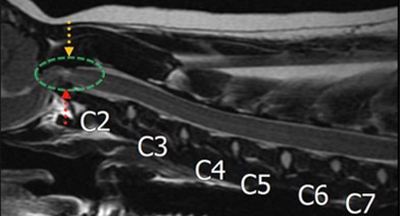

경추 디스크

Cervical IVDD 목 부위

경추 디스크는 목 부위 디스크가 탈출하거나 돌출되면서 척수를 압박해 목 통증, 보행 이상, 신경학적 증상을 유발하는 질환입니다. MRI를 통해 병변 위치와 압박 정도를 정확히 평가한 후, 환자의 신경 상태에 따라 보존적 치료 또는 감압 수술을 시행하여 척수 압박을 해소하고 신경 기능 회복을 돕습니다.